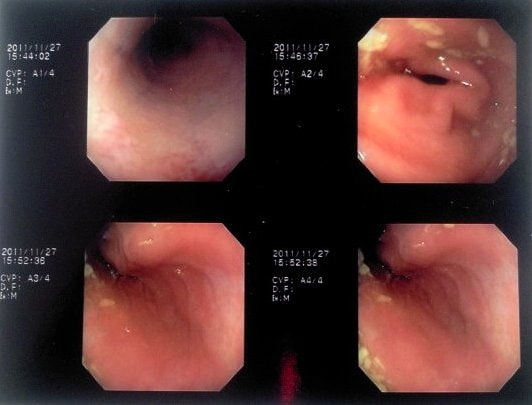

症例:炎症性ポリープ M.ダックス 10歳 オス

主訴:8ヶ月前から便が細くなり、血が混じることがある。その他、元気・食欲等、一般状態は良好。

経過:超音波検査にて直腸壁の肥厚(5㎜)が認められた。また、直腸検査で直腸全周に結節状病変を触知し、出血も確認された。消炎剤、抗生剤、整腸剤による治療への反応が長期的に悪いため、生検も含めた内視鏡検査を実施した。

内視鏡検査:肛門付近の直腸全周に、炎症および出血を伴う結節状病変を多数認めた。

病理検査:直腸の病変は、良性の非腫瘍性病変の一つである“炎症性ポリープ”と診断された。

診断後経過:炎症性ポリープは多発する傾向や腫瘍に転化する可能性があるため、消炎剤、抗生剤、整腸剤による内科療法を継続しながら、現在プルスルー法による外科的摘出術を検討中。

◎炎症性ポリープとは

近年、ミニチュアダックスで好発が知られている良性の腫瘍性の病変です。しばしば多発し、また腫瘍に転化する事があります。